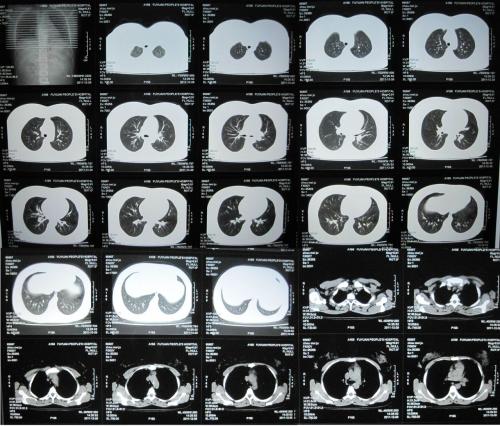

03、CT --Computed Tomography

▲ CT像把面包切片看

1972年,亨斯费尔德在英国放射学年会上正式宣告了CT的诞生。其实CT检查也是利用X线原理,只是会从各个方向对人体部位进行扫描,通过计算机重建出断层切面图像。就好比将面包切片看,但是辐射大于X光。

CT可以较好地显示由软组织组成的器官,主要应用于肺部、骨性疾病、急诊外伤、早期脑出血、钙化、胆道泌尿系结石、血管性疾病等。

3、胸部 粗看X线光片,细看CT,可以检查出肺部钙化点、结节等。低剂量螺旋CT与传统CT相比而言,扫描时间更短,辐射更小,分辨率更高。核磁就相对局限啦。